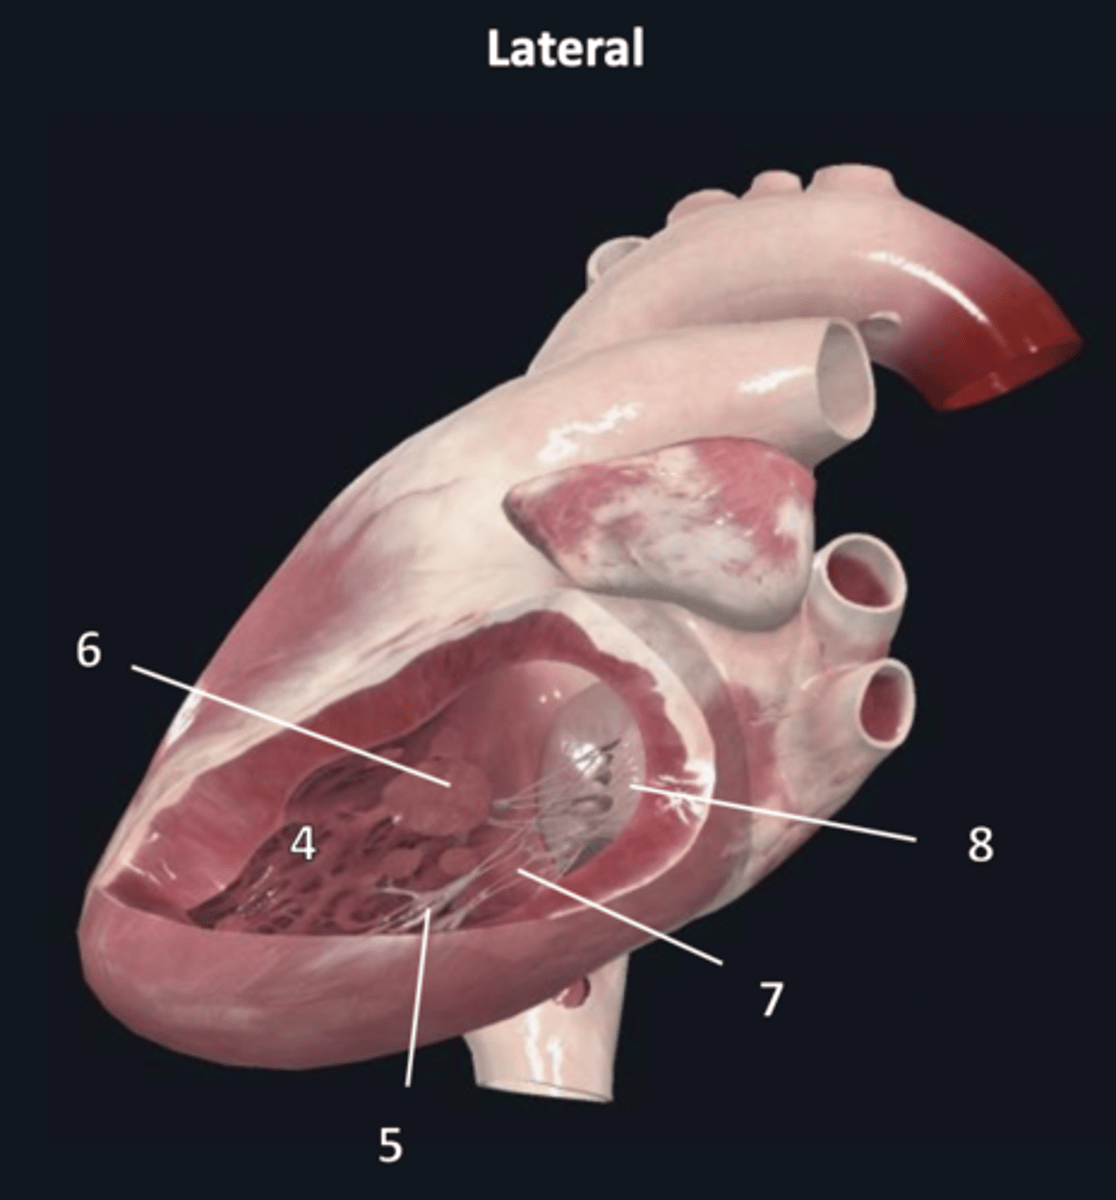

left atrium

1

left auricle

2

left ventricle

3

trabeculae carneae

4

inferior papillary muscle

5

superior papillary muscle

6

chordae tendineae

7

left atrioventricular valve

8 (opening)

aortic semilunar valve

9 (opening)